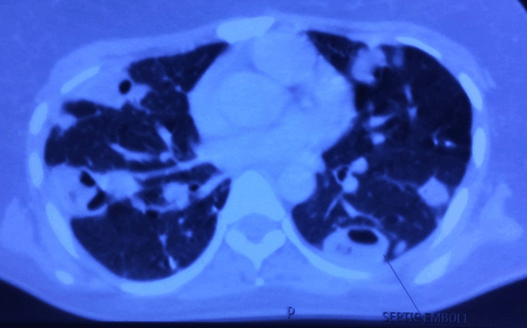

A computed tomography angiography chest (Figure 3) and neck (Figure 4) was done which revealed thrombosed left internal carotid artery (ICA), partially thrombosed left IJV, sphenoid sinusitis and cavitation in bilateral lung fields suggestive of septic emboli. Color doppler bilateral neck was done to assess the extension of thrombus in the vessels. Surprisingly, it showed involvement of both IJV (partially occluded) and ICA (80% occluded) of left side.

Figure 3: Contrast-enhanced computed tomography chest showing septic emboli.